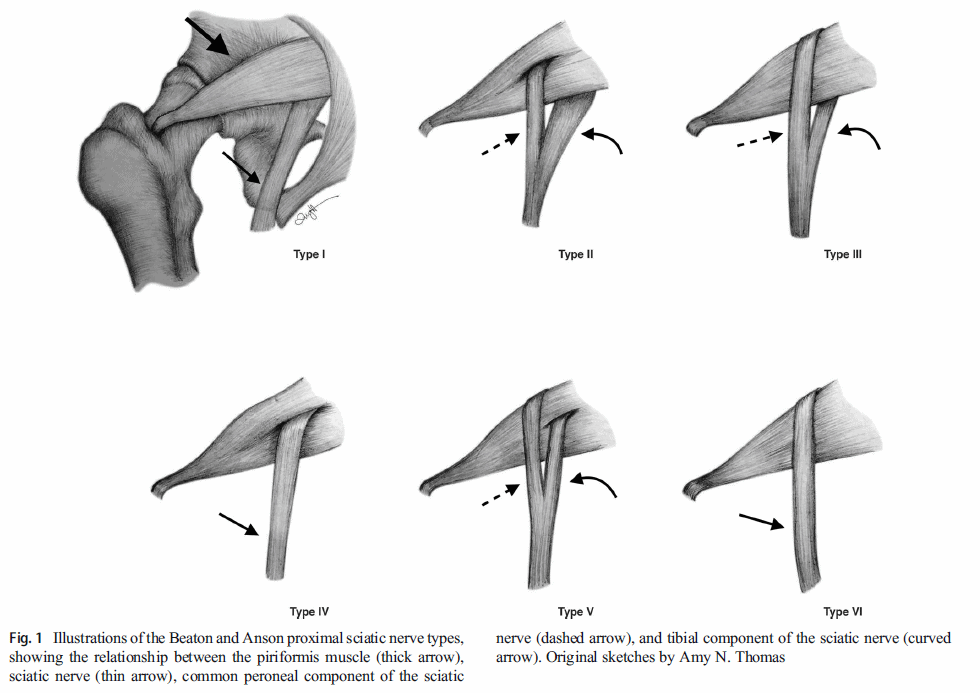

梨状肌从骶骨一直延伸到髋关节。 由于坐骨神经从梨状肌下方穿过,有人认为梨状肌紧绷可能会压迫坐骨神经,导致臀部和腿后部疼痛。 研究人员甚至发现了坐骨神经直接穿过肌肉的解剖变异,理论上坐骨神经更容易受到影响。

除了梨状肌,还有更多的解剖结构可能会压迫坐骨神经。 因此,现在更倾向于使用 "臀深综合征 "这一术语。

然而,还有更多的解剖结构可能会压迫坐骨神经,例如 Gemelli-obturator internus 复合体、腿筋肌肉、含有血管的纤维带、血管异常和空间占位性病变。 因此,专家们现在更倾向于使用 "臀深综合征 "这一术语。